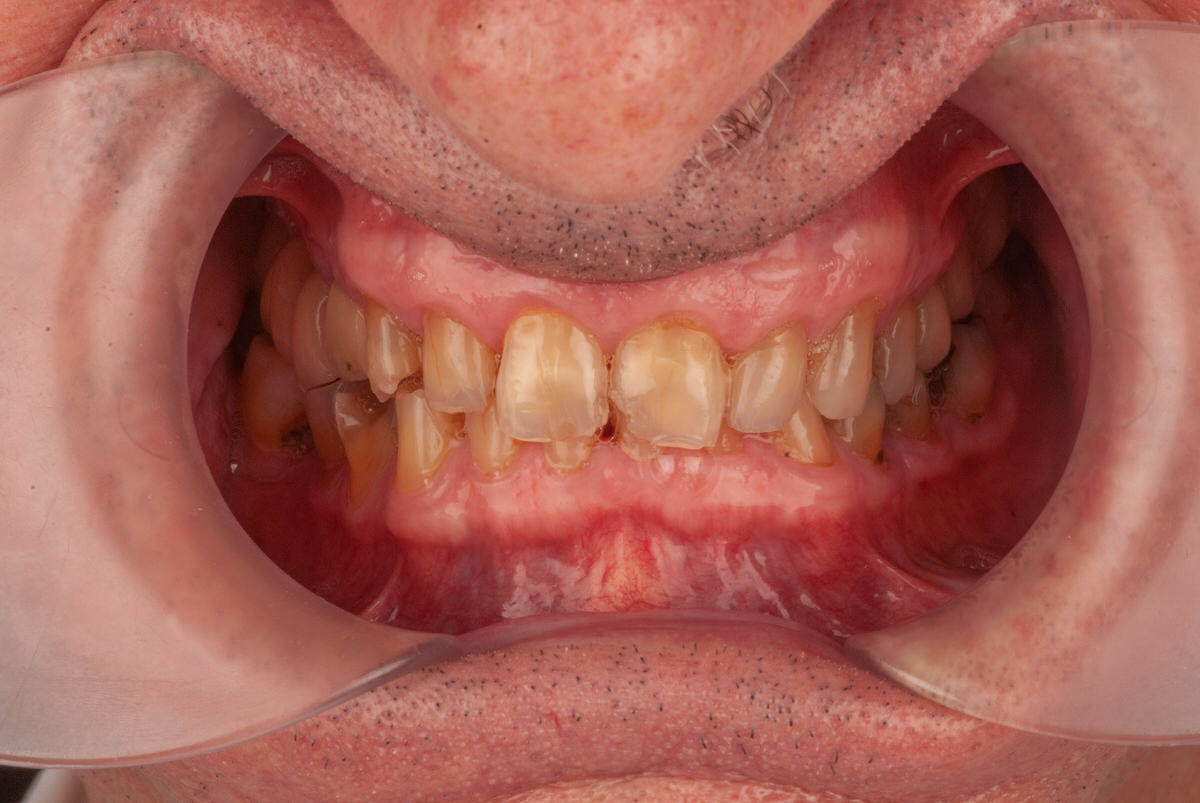

Caso Real: Rehabilitación de un Paciente con Bruxismo Severo

Diagnóstico de Bruxismo

Este paciente llegó a nuestra clínica en Hondarribia con un caso de bruxismo muy marcado. Sus dientes presentaban un desgaste severo, especialmente en los incisivos centrales, que mostraban una apariencia traslúcida debido al desgaste extremo. La mordida estaba colapsada, con los dientes superiores cubriendo excesivamente a los inferiores.

Desafío del Tratamiento

La dificultad principal en este caso radicaba en que el paciente, al ser capaz de desgastar su propio esmalte, también podría dañar cualquier restauración dental. Por lo tanto, no podíamos simplemente reparar los dientes más desgastados; era necesario rehabilitar tanto los dientes superiores como los inferiores.